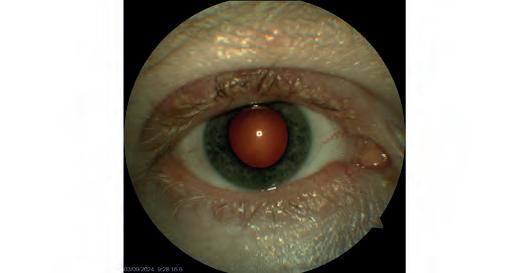

A retinal detachment diagnosed by Queensland optometrist Peter Choc on his Optos Daytona.

A secondary retinal detachment.

Images: Gladstone Vision.